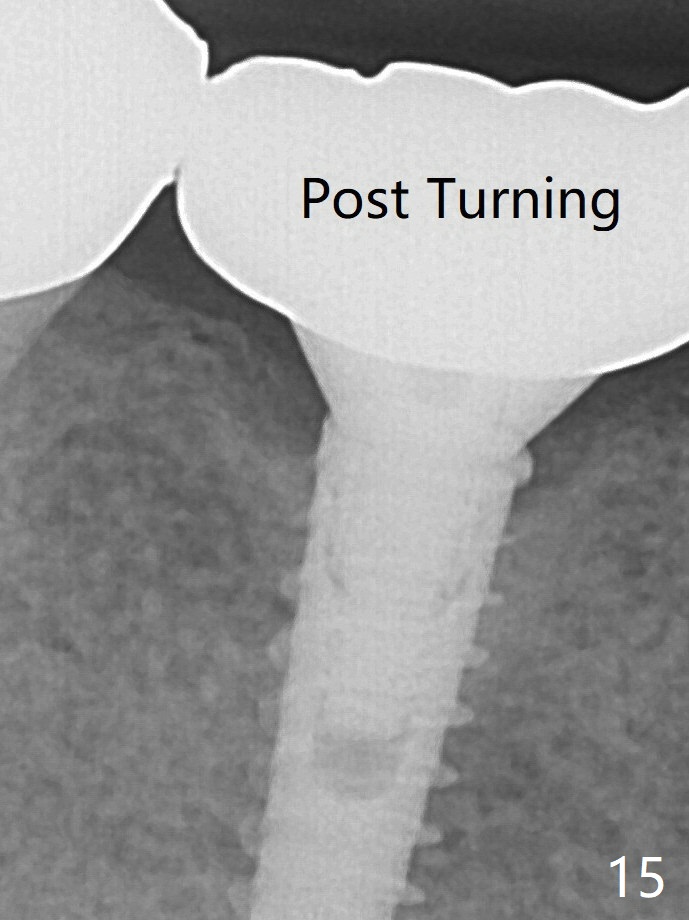

After turning, the abutment appears to be completely seated (Fig.15 (3 years post cementation), as compared to Fig.11 (both bitewing)).  远中间隙还不够,第一基台可能还没有完全被动就位,第二,邻面大一些间隙容易让取模材料进入邻面,包绕牙冠